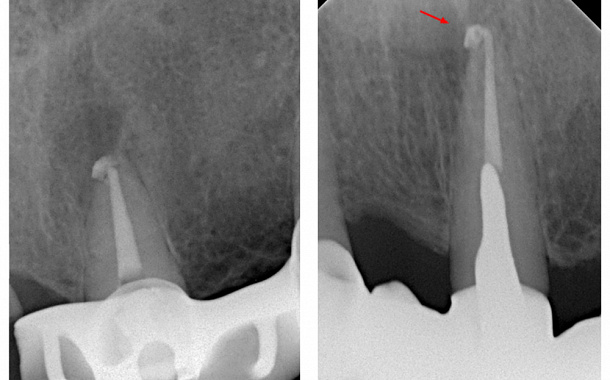

Глубокий кариес – распространяется на зубную пульпу, где находятся нервы и кровеносные сосуды, ведет к тотальному разрушению структур зуба с частичным вовлечением в процесс пульпы зуба. Глубокий кариес может вызвать острую боль и требует срочного лечения.

Пациент может жаловаться на боль в зубе, возникающую от механических или химических раздражителей. При осмотре доктор обнаруживает глубокую кариозную полость, в которой находится размягченный дентин. Иногда отмечаются ноющие болевые ощущения в зубе, сохраняющиеся после удаления раздражителя. Если разрушение затрагивает пульпу, для восстановления зуба потребуется лечение корневых каналов.

- Проведение корневого каналоведения в случае поражения зубной пульпы.